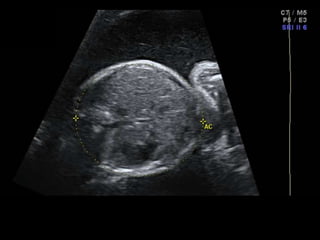

Dr. Ana Lourenco

HISTORY

• 36 yo female 30.5 weeks pregnant

• Referred with ‘multiple fetal anomalies’ for

fetal ultrasound

LUS – Cephalic

• What are the findings?

• What is the diagnosis?